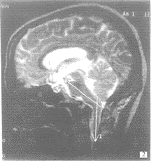

图2 颅底凹陷症患者,延髓、上段颈髓轴线夹角明显小于正常值

3.1 颅底凹陷症是以枕骨大孔为中心的颅底向上凹陷及齿突上移畸形 多数因第1、2颈椎和枕骨先天发育异常所致,如寰椎枕化、寰枢椎半脱位等。枕骨变扁,枕骨大孔偏斜,前后径变短。此外,本病亦可发生于使颅底软化的后天性疾病,如畸形性骨炎、软骨病、甲状旁腺机能亢进、类脂质沉着及老年骨质疏松等。临床症状的产生主要是因为脊髓、延髓、小脑受压,主要表现为听神经受累、眼球震颤和共济失调,脑积水,也可有副神经和颈神经根受累的症状。对于颅底凹陷症的诊断过去以常规X线摄影为主[1-3],主要通过头颅X线片分析颅底、枕骨大孔和齿突的相互关系,其测量方法较多,如测量枕鄂(Chamberlain)线、McGregor线、二腹肌沟线、Klaus线、Boogard's角、外耳孔高度指数等。MR成像不能直接观测颅底的骨骼结构,但能够直接观察病变区域延髓、脊髓、小脑受压的状况,较常规X线摄影能够更为直接和准确的反应出病变的程度[4,5]。由于正常人延髓-脑桥轴线与上颈髓轴线有一自然夹角,颅底凹陷症患者常常由于延髓受压致使该交角变小(图2),但目前为止,尚未见有文献报导该正常情况下该夹角自然角度的大小,本文通过对100名发育正常、无中枢神经系统症状及体征的成年国人该角度的测量,总结出国人该角度大小的正常参考值范围为:143.64°~165.42°(95%可信区间),根据6例颅底凹陷症患者测得的数据推测该类患者延髓-上颈髓之轴线夹角应在124.84°~131.16°之间(95%可信限),两者没有交叉。我们认为当该角度在132°~143°之间时,可以称为处于“临界状态”,此时究竟能否诊断为颅底凹陷症尚需根据临床症状综合综合考虑。